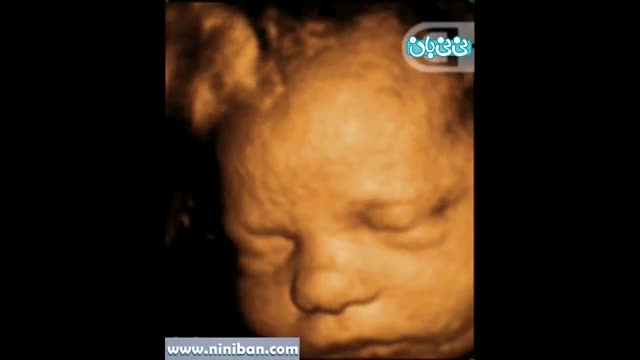

سونوگرافی چهار بعدی در بارداری هفته سی و پنجم